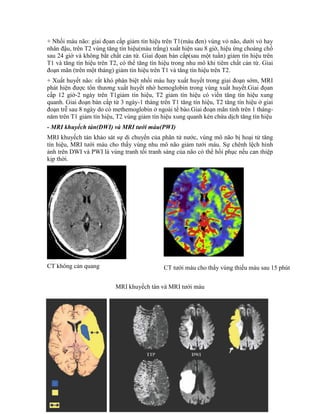

CT là xét nghiệm chọn lựa hàng đầu trong TBMMN, tuy nhiên trong nhồi máu tối cấp, đa

số cho kết quả âm tính. Trong trường hợp điều trị tiêu sợi huyết việc chẩn đoán cần phải

chính xác đòi hỏi phải dựa vào MRI

- Các thay đổi của MRI trong TBMMN

+ Nhồi máu não: giai đọan cấp giảm tín hiệu trên T1(màu đen) vùng vỏ não, dưới vỏ hay

nhân đậu, trên T2 vùng tăng tín hiệu(màu trắng) xuất hiện sau 8 giờ, hiệu ứng choáng chổ

sau 24 giờ và không bắt chất cản từ. Giai đọan bán cấp(sau một tuần) giảm tín hiệu trên

T1 và tăng tín hiệu trên T2, có thể tăng tín hiệu trong nhu mô khi tiêm chất cản từ. Giai

đoạn mãn (trên một tháng) giảm tín hiệu trên T1 và tăng tín hiệu trên T2.

+ Xuất huyết não: rất khó phân biệt nhồi máu hay xuất huyết trong giai đoạn sớm, MRI

phát hiện được tổn thương xuất huyết nhờ hemoglobin trong vùng xuất huyết.Giai đọan

cấp 12 giờ-2 ngày trên T1giảm tín hiệu, T2 giảm tín hiệu có viền tăng tín hiệu xung

quanh. Giai đoạn bán cấp từ 3 ngày-1 tháng trên T1 tăng tín hiệu, T2 tăng tín hiệu ở giai

đoạn trễ sau 8 ngày do có methemoglobin ở ngoài tế bào.Giai đoạn mãn tính trên 1 tháng-

năm trên T1 giảm tín hiệu, T2 vùng giảm tín hiệu xung quanh kén chứa dịch tăng tín hiệu

- MRI khuyếch tán(DWI) và MRI tưới máu(PWI)

MRI khuyếch tán khảo sát sự di chuyển của phân tử nước, vùng mô não bị hoại tử tăng

tín hiệu, MRI tưới máu cho thấy vùng nhu mô não giảm tưới máu. Sự chênh lệch hình

ảnh trên DWI và PWI là vùng tranh tối tranh sáng của não có thể hồi phục nếu can thiệp

kịp thời.

CT không cản quang

MRI khuyếch tán và MRI tưới máu

CT tưới máu cho thấy vùng thiếu máu sau 15 phút

Cấp

Sau 3 ngày

- Lõi họai tử

- Vùng tranh

tối tranh sáng